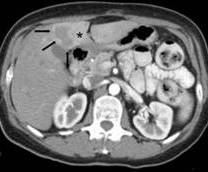

Hình ảnh trên chụp cắt lớp vi tính cho thấy ổ tổn thương giảm tỉ trọng, ngấm ít thuốc ngoại vi, cần phân biệt với áp xe gan và tổn thương di căn gan (mũi tên đen). Khi đó làm xét nghiệm ELISA dùng kháng nguyên ấu trùng giun toxocara rất có giá trị. Tuy nhiên khi phân biệt với tổn thương di căn gan, cần làm thêm các xét nghiệm khác như chỉ điểm u (CEA, CA 19-9, CA 72-4, aFP….) và tiến hành nội soi dạ dày, nội soi đại trực tràng….